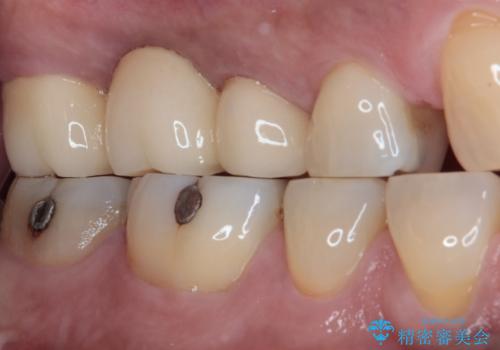

- 奥歯のブリッジに違和感があるとのことで来院された患者様です。

土台となっている最後方の歯に痛みがあるようで、むし歯処置あるいは根管治療を行う前提で金属ブリッジを除去することとしました。

ブリッジ除去後痛みが引いたことを確認し、オールセラミックブリッジによる補綴治療を行うこととしました。

銀歯に隠れていて術前のレントゲンでははっきりと分かりませんでしたが、元々非常に大きなむし歯があったようで、銀歯の中で神経組織が壊死を起こしていました。

速やかに根管治療を行い、無事に痛みを取り除くことができました。